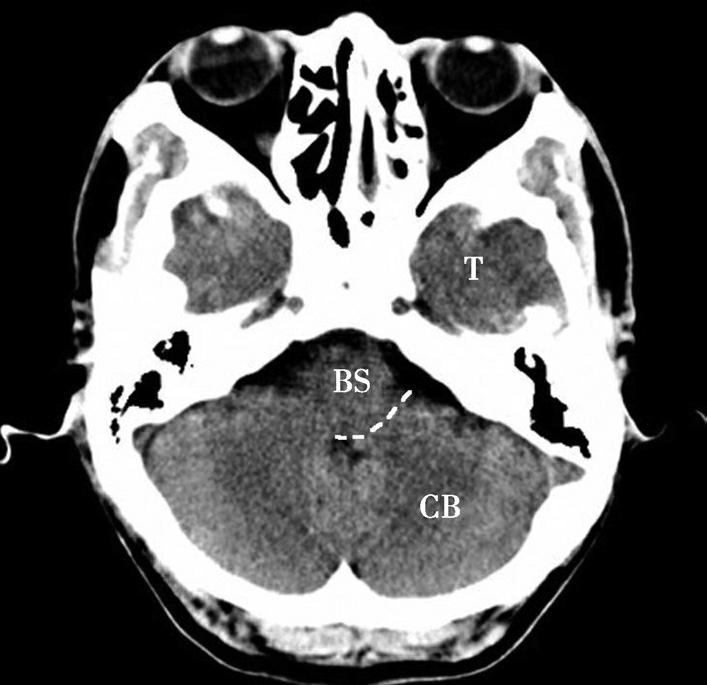

CB.小脑;BS.脑干;T.颞叶

蝶骨体占据层面中部,内部可见蝶窦,中间有骨性分隔。蝶骨体前方正中为鼻中隔,鼻中隔两侧为蜂窝状含气骨性腔隙,即筛窦,筛窦前方为鼻骨。筛窦两侧可见两侧对称的圆形眼球断面位于眼眶内,眼球壁呈厚薄均匀的环状,称为眼环。玻璃体位于眼环内呈均匀低密度影,晶状体位于玻璃体前方,呈双凸透镜状高密度影,眼球后方为锥体形的眶脂体,其内正中可见视神经通行,眶内侧壁与筛窦间隔以菲薄的纸板,眶外侧壁由额骨眶突和蝶骨大翼构成,内、外直肌紧贴眶壁走向眶尖,视神经管位于眶尖。位于蝶窦两侧的有颞叶、颞骨鳞部及颞骨外侧的颞肌。蝶窦后方为斜坡,斜坡后外侧为颞骨岩部尖,后外方为乳突,其内可见乳突小房呈蜂窝状,岩部的内后缘可见两侧对称的内听道,其内第Ⅶ、Ⅷ对脑神经CT上无法分辨,听神经瘤常伴有内听道的扩大(图1-2-8)。内听道后外方的骨性空腔为中耳鼓室。枕骨斜坡及岩骨后方为颅后窝,脑桥位于其前部,脑桥后方可见第四脑室,其后方为小脑蚓部。小脑半球以小脑中脚与脑桥相连,脑桥与斜坡之间为桥前池,其向两侧延伸的部分呈三角形,两侧对称,位于脑桥、小脑中脚及岩骨之间,称为脑桥小脑角池。位于脑桥小脑角池的常见病变有听神经瘤、三叉神经瘤、脑膜瘤和胆脂瘤等(图1-2-9)。